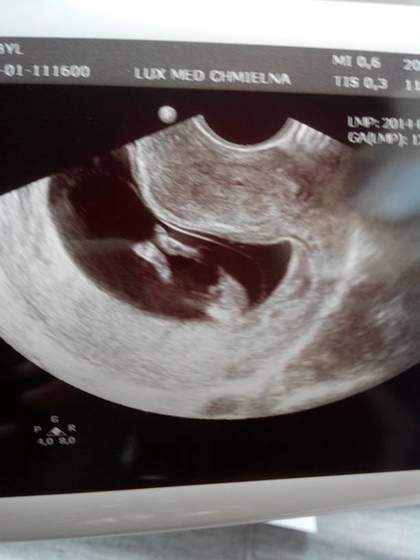

Dzidziusiowe USG :)

to 11 tydz i 3 dzien wg OM, ale maluszek "zaskoczyl" pozniej jednak widze spora różnicę do tego co było 3 tyg temu :-)

Poznajcie ciotki !:)